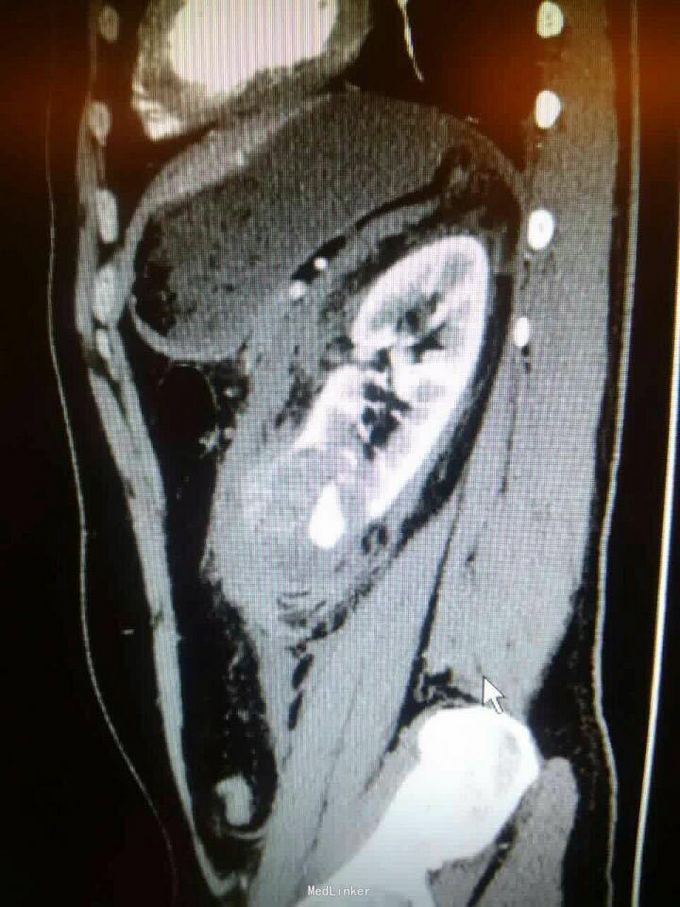

左肾下级错构瘤破裂伴出血

发现错构瘤五年余,破裂3小时

泌尿系ct

肾挫伤,及时手术治疗,行肾脏全切术

为了保险起见,还是全切,未保肾,都不敢去保